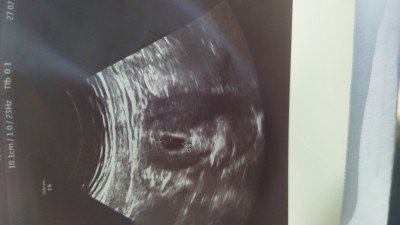

Herkese merhaba birkez kimyasal gebelik geçirdim 6+2 haftalıgm keseyi dün gördük içinde beyaz bişey var sanırım ama emin olmak için haftaya gel dedi sizce bebek keseye dustu mü ? Bu arada fotograf yansekilde yüklendi telefonu sağ tarafa döndürüp bakıp lütfen şimdiden teşekkürler

Slm bendede böyleydi 8 haftalıkken görmüştüm bebeğimi o beyaz olan şey muhtemelen yolk kesesi inşallah vardır

Kuzum orada yuvarlak olan şey yolk sac Allah sağlıklı doğum nasip etsin hayırlı olsun

Hayır canım yolk sac bebegın beslendıgı yuvarlak bır kan kesesı kesenın ıcınde oluşan eğer o varsa bebek var demektır

Canim o cember seklinde yolk sac bebek olusmadan once o olusuyor bebek olusunca kendi kendine kayboluyor ama bos gebelik te olusmuyor bu bebeginizin olusacagini gosteriyor

Yorumlarda da belirtmişler zaten beyaz görünen şey muhtemelen yolks sac kesesi. Haftaya bebeği de kalp atışını da görürsünüz inşallah:-)